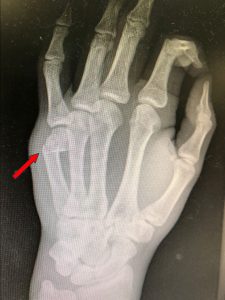

Luxaciones interfalángicas: (Figura 1) Son frecuentes, especialmente en el dedo anular o meñique. Se producen por impactos mal alineados o por golpear con la mano abierta. Pueden requerir reducción y en algunos casos, inmovilización o cirugía si hay lesiones ligamentosas asociadas.

Figura 1 - Luxación interfalángica.